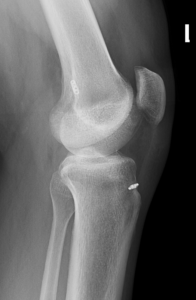

Diagnosis

An ACL injury can be diagnosed with a thorough physical examination of the knee and diagnostic tests such as X-rays, MRI scans and arthroscopy. X-rays may be needed to rule out any fractures. In addition, your doctor will often perform the Lachman’s test to see if the ACL is intact. During a Lachman test, knees with a torn ACL may show increased forward movement of the tibia and a soft or mushy endpoint compared to a healthy knee.